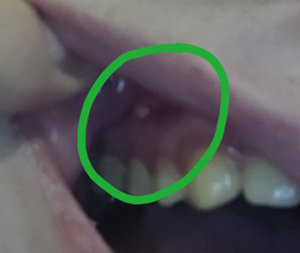

Подскажите, пожалуйста. Болела десна около недели, незначительно. Позже образовался какой-то шарик, похожий на прыщик. А после, во время еды что-то стало мешать и вот появилось непонятное новообразование из десны. На ощупь твердое, беспокоит во время приема пищи.

Подскажите, что это может быть?

Очень сложно определить, но все Ваши симптомы говорят и свищевом выходе. То есть, на верхушках зуба имеется воспалительный процесс.